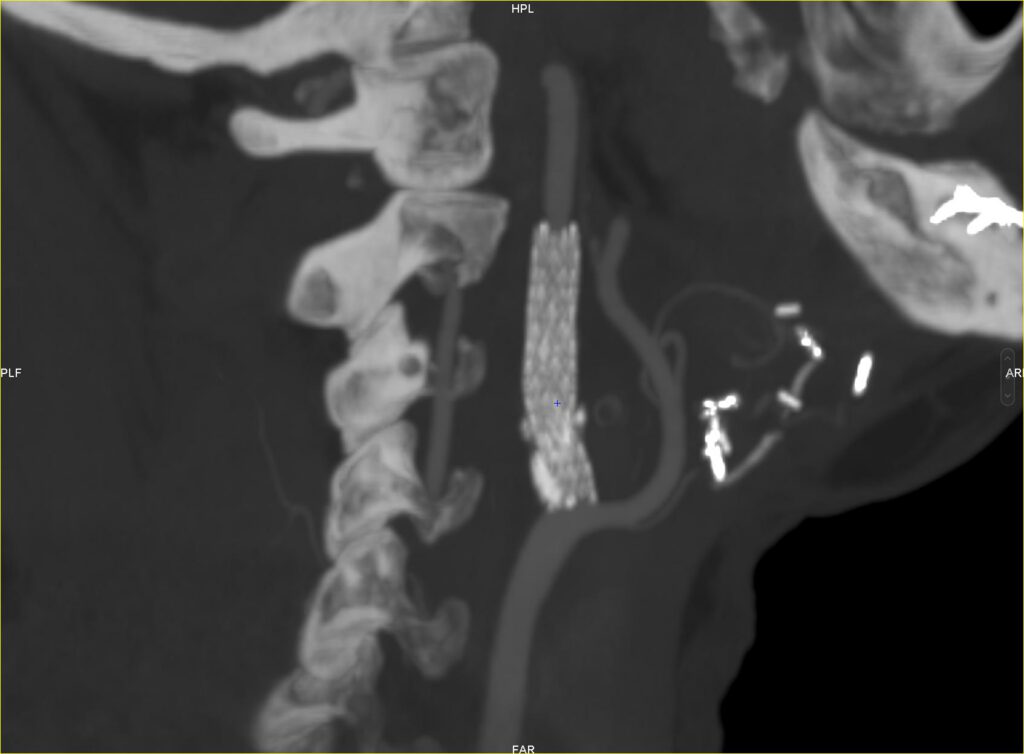

Après une ponction artérielle (piqûre), un cathéter (petit tuyau souple) est introduit soit dans l’artère fémorale commune droite au niveau du pli de l’aine soit dans l’artère radiale au niveau du poignet. Un cathéter est ensuite dirigé en temps réel sous guidage radiologique vers l’artère carotide pathologique. Une cartographie des artères carotides (artériographie) est alors réalisée en injectant du produit de contraste par le cathéter afin de bien évaluer l’étendue et le degré de rétrécissement de la carotide et réaliser ainsi un planning opératoire précis (zone d’inflation du ballon et de mise en place du stent).

On passe alors la sténose (rétrécissement) avec le cathéter puis on réalise alors soit directement la mise en place du stent (angioplastie stenting), soit il est parfois nécessaire réaliser une prédilatation au ballon (angioplastie au ballon) avant de mettre en place le stent. On réalise enfin une dernière artériographie pour confirmer la bonne efficacité de l’intervention. L’anesthésie est alors diminué et le patient est transféré en salle de réveil.